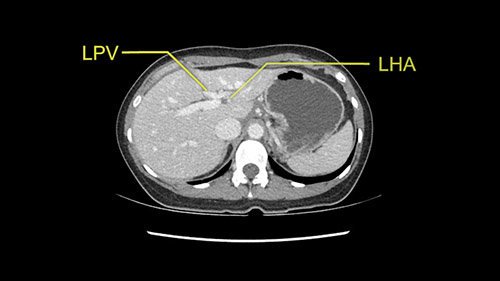

So if we look at the CT scan, on the axial, it’s a larger lesion. It’s about 6 or 7 or 8 centimeters. So it does look a bit threatening in terms of its resectability but if you really drill down deeply into the anatomy, and I think the coronal [imaging] is even better, you can see that the entire mass is on the patient’s left side of the falciform ligament. So it’s really only a left-sided tumor and not even really a left-sided tumor because Segment 4 is uninvolved anatomically.

Anatomically, to plan for a left lateral segmentectomy, it’s relatively easy as far as liver surgery goes. I know that I'm going to be looking for the left hepatic vein which will be divided at some point either towards the end at the back near the vena cava or through the middle of the left lateral segment.

Inflow is not usually an issue except if there are as a replaced or aberrant left hepatic artery. In which case you’d be careful when you mobilize the left lateral segment.

Dissection of left portal vein

Sg2-3 left hepatic artery

As I review the CT scan, we have both arterial and venous phases, the tumor is obvious. But I’ll start by saying that the liver itself does not appear to be cirrhotic to my eye. It’s got a normal contour and allied to that, that I do not see evidence of portal hypertension. The spleen is normal, there’s no collateral vessels. The tumor itself, I measured maximally at about 11 centimetres in diameter and I’m told the alpha fetoprotein is very high (over 10000), which is entirely consistent with this being a solitary hepatocellular carcinoma that is very exophytic. It seems to emanate off the inferior margin of Segment 3 (because that’s the falciform). I’ll start by saying that this is not transplantable. The tumor exceeds our guidelines for transplantation, but it's likely resectable based on normal liver and no portal hypertension.

So the issue with regards to resection. A left sided tumor. I believe I can see the falciform ligament right here so we’re looking at a resection of Segments 2, 3 of the left lobe of the liver. The left portal vein is right there. I think we’ll be wiser to take the left portal vein and therefore get well into Segment 4 and do a left hemihepatectomy. Certainly, one does not need to take the middle hepatic vein; it’s miles from the tumor.

So I have to say that I would do this open, not laparoscopically because of the size of the tumor itself. Upper abdominal incision. Almost certainly, we’d be able to flip this very exophytic lesion up. Intraoperative ultrasound will show the relationship of the tumor and the left portal vein but the dissection at the base of the liver, as I look at things here, I can see the left hepatic artery which sneaks up to the left of the portal vein, should be out of harm’s way so I can take the Segment 2-3 left hepatic artery. The left portal vein is somewhat compressed. But by the time you pull the liver up a bit, you’ll be able to pull that left portal vein out to length and get a good margin on it.

My plan would be to leave the caudate lobe intact. You usually have to divide the caudate branches. I can see one of the caudate branches here coming off the left portal vein. You usually have to take that to get adequate length although you might be able to divide the portal vein past that left caudate branch.

Now let’s look at some specific anatomical points for planning this surgery. First thing you see when you see a left hemihepatectomy is that where is the left portal vein and the right portal vein branching? And what is the stump of the left portal vein available for you for ligation? In this particular case, you’ll find that there’s overhanging of the tumor but left portal vein pedicle is sufficiently available for us for ligation.

The second is the left hepatic artery. The tumor is displacing the arterial system. So one of the important points which we need to see intraoperatively is to identify and preserve the right artery very carefully and identify the left hepatic artery for ligation.